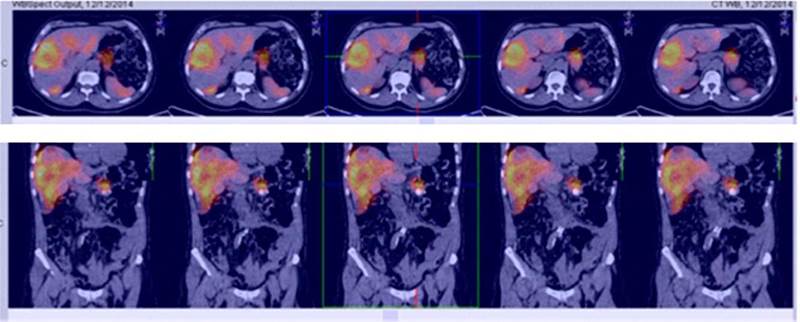

Para el manejo sintomático el paciente fue hospitalizado y se le administró diazoxido 50 mg vía oral cada 8 horas sin lograr un adecuado control al cabo de dos días, con una mala tolerancia al aumento de la dosis. Requirió la infusión continua de dextrosa al 10% en agua destilada (DAD10%) y se le practicó una prueba de respuesta a octreotide subcutáneo1 con monitoreo glucométrico durante 6 horas (tabla 2) sin lograr una repuesta adecuada, presentando incluso hipoglucemia pese a que la gammagrafía con HYNIC-TOC (octreotide-tecnecio-99) encontrara sobreexpresión de receptores de somatostatina en las lesiones hepáticas y en la lesión del cuerpo del páncreas (fig. 2). Se discutió el caso en una junta multidisciplinaria y se decidió realizar embolización arterial hepática (EAH) de las lesiones de mayor tamaño localizadas en los segmentos v y v, procedimiento que fue realizado intrahospitalariamente (fig. 3) sin complicaciones, y alcanzando un control sintomático a las 24 horas del mismo. De manera inesperada posterior al procedimiento desarrolló hiperglucemias persistentes, lo que requirió el uso de insulina para su manejo.

Figura 2 Fusión HYNIC-TOC (gammagrafía octreotide-tecnecio) + IRM de abdomen: muestra los sitios de sobreexpresión de receptores de somatostatina.